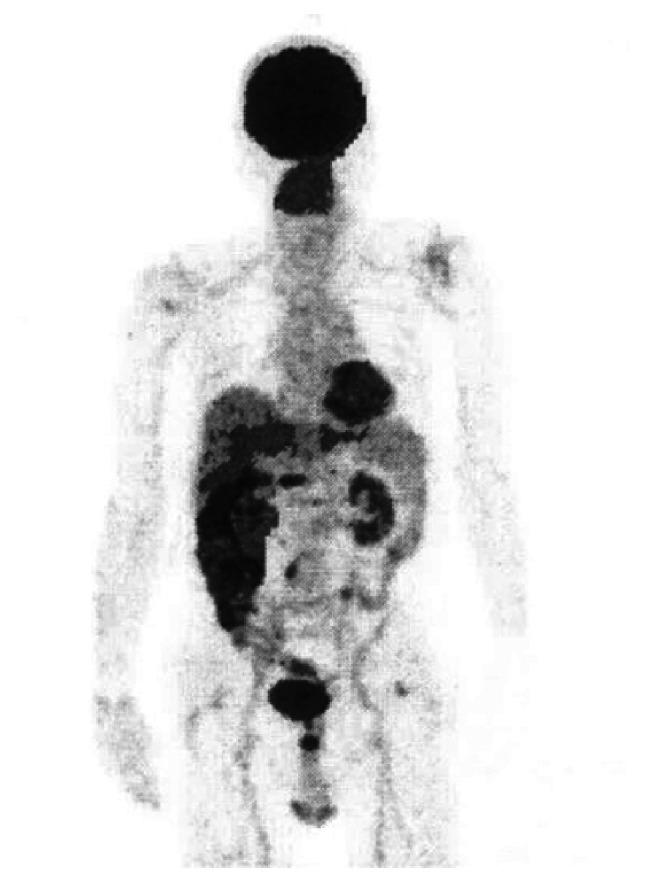

Colorectal metastasis from gastric cancer is rare and may develop several years after gastric cancer surgery. Therefore, colonoscopic findings provide useful diagnostic information. The present report describes a case of gastric cancer colon metastasis diagnosed 8 years and 10 months after gastrectomy for advanced gastric cancer. A 64-year-old male patient underwent gastrectomy in December 2010 and received chemotherapy for 4 years and 10 months after the surgery. Subsequently, the patient was diagnosed as having colorectal cancer by computed tomography in February 2019. Colonoscopy revealed linitis plastica-like colon stenosis; however, biopsy pathology did not reveal any findings indicating malignancy. Right hemicolectomy was performed, and pathological examination revealed colon metastasis from gastric cancer. The patient received chemotherapy but died of peritoneal carcinomatosis 1 year and 8 months after the colectomy. According to literature, colorectal metastasis from gastric cancer is often attributed to hematogenous metastasis and often exhibits characteristic macroscopic features. Treatments, such as chemotherapy for gastric cancer and/or colorectal resection, are considered effective for gastric cancer colorectal metastasis.

胃癌的结直肠转移罕见,且可能在胃癌手术后数年发生。因此,结肠镜检查结果可提供有用的诊断信息。本报告描述了1例进展期胃癌胃切除术后8年10个月被诊断为胃癌结肠转移的病例。一名64岁男性患者于2010年12月接受胃切除术,术后接受了4年10个月的化疗。随后,该患者于2019年2月经计算机断层扫描被诊断为结直肠癌。结肠镜检查显示皮革胃样结肠狭窄;然而,活检病理未发现任何提示恶性肿瘤的迹象。患者接受了右半结肠切除术,病理检查显示为胃癌结肠转移。患者接受了化疗,但在结肠切除术后1年8个月死于腹膜癌。根据文献,胃癌的结直肠转移通常归因于血行转移,且常表现出特征性的宏观特征。对于胃癌结肠转移,诸如胃癌化疗和/或结直肠切除术等治疗方法被认为是有效的。